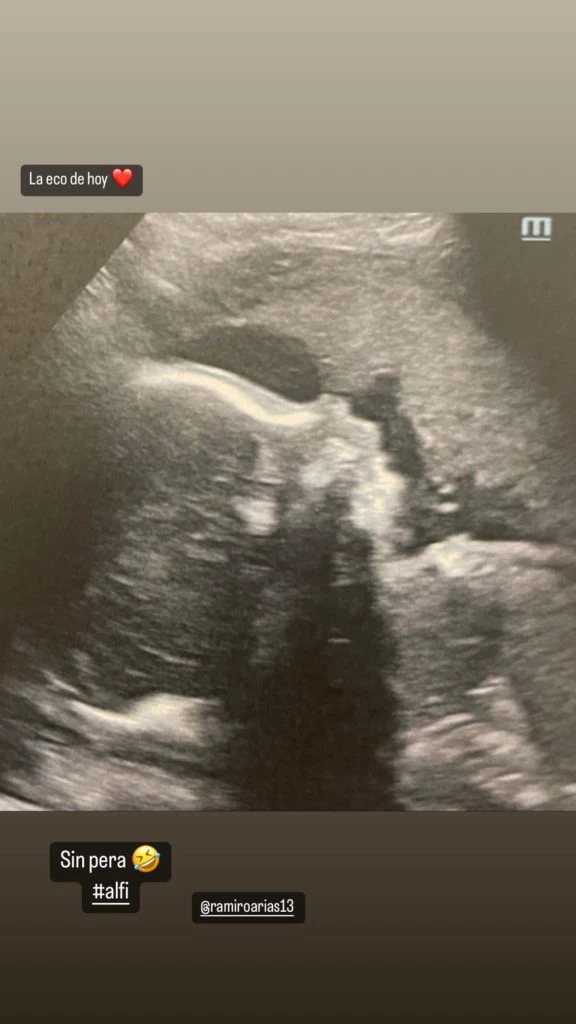

Finalmente, la bailarina publicó una reciente ecografía de Alfonsina, para aclarar que no hubo ningún tipo de riesgo con la bebé. "Estamos regias. Con exceso de cuidado y amor. Los amo”, finalizó, sin antes agradecer a sus seguidores por los mensajes de apoyo y la preocupación transmitida.